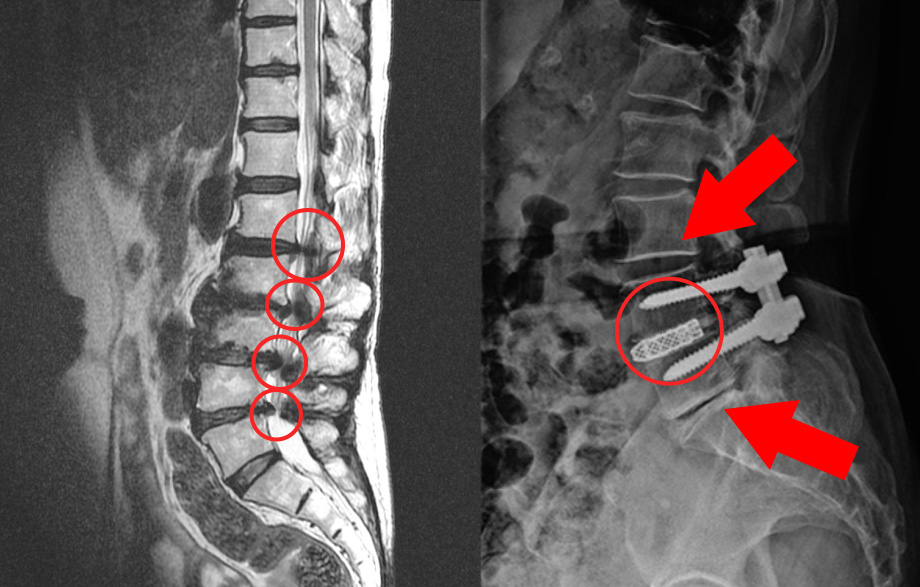

- X선: X선 촬영을 통해 뼈의 구조를 시각적으로 확인하고, 퇴행성 변화나 이상 여부를 확인할 수 있습니다.

- MRI 또는 CT 스캔: 이러한 고급 이미징 기술을 통해 신경 및 연부조직의 압박 상태를 더욱 상세히 확인할 수 있습니다.

- 수술적 치료: 보통 보존적 치료로 효과를 보지 않는 경우, 수술을 고려할 수 있습니다. 이는 압박된 신경을 자유롭게 하고 척추를 안정시키는 방향으로 진행됩니다.